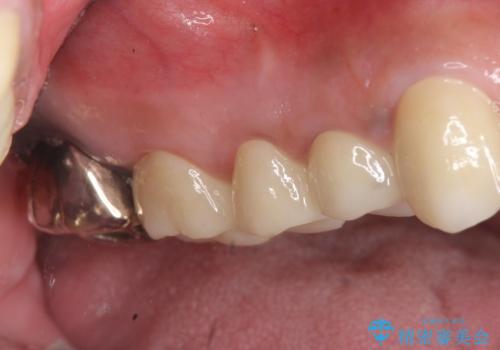

インプラントは希望されなかったため、左側は1番から7番のロングスパンブリッジによる補綴を行いました。

今回用いたオールセラミッククラウンは、ジルコニアフレームという白い素材の上にセラミックを盛っているため審美性が非常に高いのが特徴です。

またジルコニアは人工ダイヤモンドの材料にも使われているほど高い強度を持っており、そのためオールセラミッククラウンは審美性だけでなく、奥歯やブリッジの補綴も可能とするクラウンです。